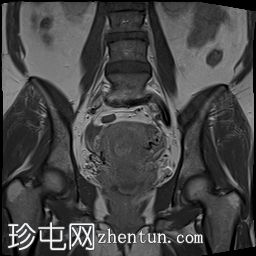

冠状位

T1加权像

可见子宫外腹腔内妊娠囊,内含胎儿组织。

该妊娠囊向后推移子宫,并与剖宫产瘢痕凹陷处紧密相连。

该妊娠囊与相关肠袢无法分离。可见其与性腺血管密不可分,且性腺血管明显突出。

胎盘位于妊娠囊后方,紧贴子宫前壁。

沿妊娠囊下缘可见一处异质性局灶性积液,最大轴向尺寸约为 8.4 × 5.5 cm,T1 加权像呈异质性高信号,T2 加权像呈异质性中等信号,T1 脂肪抑制序列未见信号下降,提示为血液成分。该积液压迫膀胱。

可见周围脂肪间隙呈条索状改变。

左侧卵巢无法辨认。

右侧卵巢未见实性或囊性肿块。

子宫体积增大,后倾,子宫内膜厚度约 1 cm,子宫下段前壁可见局灶性变薄(既往子宫瘢痕)。子宫连接区完整,未见肌层肿块。可见子宫内膜腔边缘有血性分泌物。